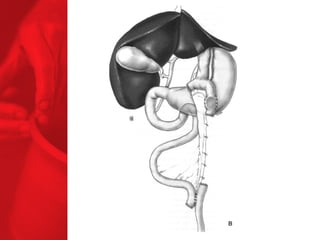

LA DIVERSION BILIO-PANCREATIQUE (DBP) Procédure de malabsorption Poche de l'estomac plus grande Plus grande perte de poids Plus grande malabsorption des nutriments Perte de surcharge pondérale de 74% la première année, 78% la deuxième année, 81% la troisième année, 84% la quatrième année et 91% la cinquième année*.   diminue le diabète de type 2 chez près de 77% des patients** *Duodenal Switch: An Effective Therapy for Morbid Obesity – Intermediate Results” Baltasar A, Bou R. Obesity Surgery 2001 Feb; 11(1): 54-8. ** Buchwald H, Avidor Y, Braunwald E, et al. Bariatric Surgery—A Systematic Review of the Literature and Meta-analysis. Journal of the American Medical Association 2004 Oct 13;292(14).

DIVERSION BILIO-PANCREATIQUE (DBP) AVEC «SWITCH DUODENAL» Procédure de malabsorption Poche de l'estomac plus grande Plus grande perte de poids Plus grande malabsorption des nutriments Perte de surcharge pondérale de 74% la première année, 78% la deuxième année, 81% la troisième année, 84% la quatrième année et 91% la cinquième année*.   Diminue le diabète de type 2 chez près de 77% des patients** *Duodenal Switch: An Effective Therapy for Morbid Obesity – Intermediate Results” Baltasar A, Bou R. Obesity Surgery 2001 Feb; 11(1): 54-8. ** Buchwald H, Avidor Y, Braunwald E, et al. Bariatric Surgery—A Systematic Review of the Literature and Meta-analysis. Journal of the American Medical Association 2004 Oct 13;292(14).

LA DIVERSION BILIO-PANCREATIQUE(DBP) Procédure de malabsorption Poche de l'estomac plus grande Plus grande perte de poids Plus grande malabsorption des nutriments Perte de surcharge pondérale de 74% la première année, 78% la deuxième année, 81% la troisième année, 84% la quatrième année et 91% la cinquième année*. diminue le diabète de type 2 chez près de 77% des patients** *Duodenal Switch: An Effective Therapy for Morbid Obesity – Intermediate Results” Baltasar A, Bou R. Obesity Surgery 2001 Feb; 11(1): 54-8. ** Buchwald H, Avidor Y, Braunwald E, et al. Bariatric Surgery—A Systematic Review of the Literature and Meta-analysis. Journal of the American Medical Association 2004 Oct 13;292(14).

DIVERSION BILIO-PANCREATIQUE (DBP)AVEC «SWITCH DUODENAL» Procédure de malabsorption Poche de l'estomac plus grande Plus grande perte de poids Plus grande malabsorption des nutriments Perte de surcharge pondérale de 74% la première année, 78% la deuxième année, 81% la troisième année, 84% la quatrième année et 91% la cinquième année*. Diminue le diabète de type 2 chez près de 77% des patients** *Duodenal Switch: An Effective Therapy for Morbid Obesity – Intermediate Results” Baltasar A, Bou R. Obesity Surgery 2001 Feb; 11(1): 54-8. ** Buchwald H, Avidor Y, Braunwald E, et al. Bariatric Surgery—A Systematic Review of the Literature and Meta-analysis. Journal of the American Medical Association 2004 Oct 13;292(14).